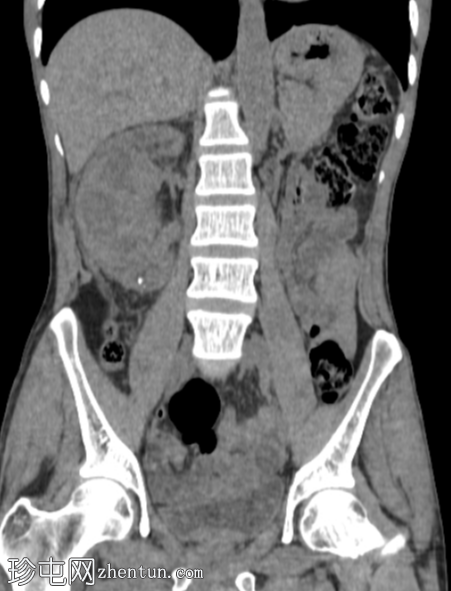

冠状位

平扫

右肾前部可见一边界清晰的外生性病变,呈异质性,包含实性及囊性成分,内部可见多发结石。肾周可见模糊影。

左肾体积缩小且萎缩,可见多发结石。

病变内部存在结石及肾周模糊影提示炎症性病变,可能为局灶性黄色肉芽肿性肾盂肾炎(XGP),而非肿瘤性肿块(肾细胞癌)。